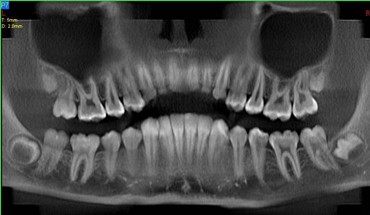

L’Unità Operativa di Radiologia Odontoiatrica, ubicata presso il Dipartimento, è dotata di apparecchiature all’avanguardia nella diagnostica odontostomatologica e del massiccio-facciale. In particolare è presente un’apparecchiatura TC Cone Beam di ultima generazione che consente l’acquisizione volumetrica ad alta definizione ed a bassissima dose dell’intero volume cranio-facciale comprese le articolazioni temporo- mandibolari e le prime vertebre cervicali. Tale esame oggi trova larga applicazione nel campo della diagnostica odontoiatrica e del massiccio facciale, come lo studio pre e post-implantare, la valutazione di elementi dentali inclusi, lo studio di lesioni odontogene e non odontogene, la traumatologia cranio-facciale ed anche la valutazione dei seni paranasali, dell’orecchio e delle articolazioni temporo-mandibolari. Grazie all’acquisizione volumetrica ed alla bassa dose di radiazioni tale metodica è oggi indicata anche nella pianificazione del trattamento ortodontico. Nell’Unità Operativa è inoltre presente l’Orthophos Plus della Sirona Dental System che consente di effettuare esami radiografici standard digitali delle arcate dentarie, dei seni paranasali e delle articolazioni temporomandibolari ed inoltre teleradiografie nelle proiezioni latero-laterale ed antero-posteriore per studio ortodontico. L’Unità Operativa è collegata in rete con i vari reparti della clinica per una rapida consultazione degli esami radiologici.

- OPT